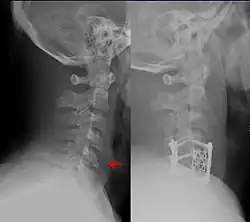

| Teardrop fracture of the cervical spine before and after treatment with metal fixation | |

A flexion teardrop fracture is a fracture of the anteroinferior aspect of a cervical vertebral body due to flexion of the spine along with vertical axial compression.[1] The fracture continues sagittally through the vertebral body, and is associated with deformity of the body and subluxation or dislocation of the facet joints at the injured level.[2] A flexion teardrop fracture is usually associated with a spinal cord injury, often a result of displacement of the posterior portion of the vertebral body into the spinal canal.[3]

The flexion teardrop fracture should not be confused with a similar-looking vertebral fracture called "extension teardrop fracture". Both usually occur in the cervical spine, but as their names suggest, they result from different mechanisms (flexion-compression vs. hyperextension). Both are associated with a small fragment being broken apart from the anteroinferior corner of the affected vertebra. Flexion teardrop fractures usually involve instability in all elements of the spine at the injured level, commonly occur at the C4-C7 vertebra, and have a high association with spinal cord injury (in particular anterior cord syndrome). In comparison, the extension-type fracture occurs more commonly at C2 or C3, causes less if any disruption to the middle and posterior elements, and does not usually result in spinal cord injury (however, it may co-occur with more serious spine injuries).[2]